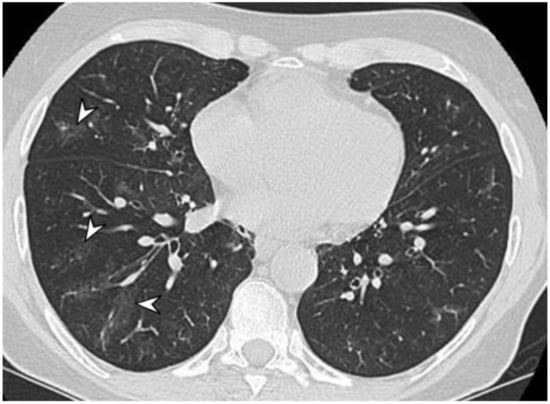

2.3. Microscopic Polyangiitis (MPA)

| MPA | GGOs due to hemorrhagic alveolitis (common); consolidation, nodules with centrilobular distribution (less common) |

| GPA | Solid nodules, GGOs due to hemorrhagic alveolitis (common); halo sign, crazy paving (less common) |